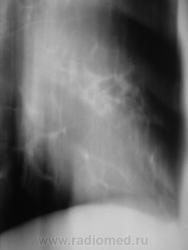

Распад был изначально, но, к счастью больного, все закончилось практическим выздоровлением.

Долго что-то пневмонию лечили. А распад очень сомнительный. Больше на игру теней похож.

Да, лечение весьма затянулось.